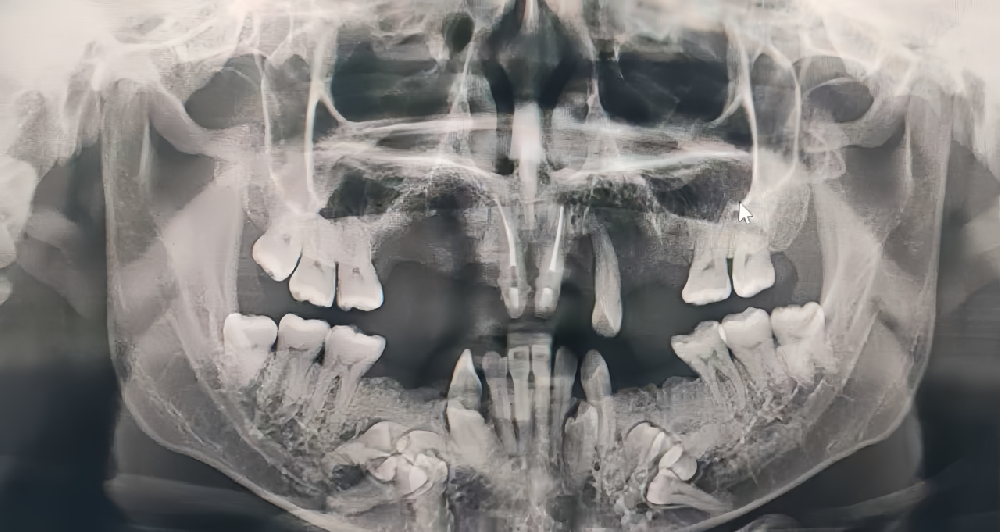

▲术前:多颗牙缺失、多颗埋伏牙、颌骨严重缺损

这位患者因多颗牙缺失严重影响工作与生活,曾四处求医,却未得到满意的治疗效果,最终慕名来到我院就诊。我院名誉院长吴纪楠带领种植修复中心蒋颖主治医师、吴业淮主治医师对患者进行了全面的口腔专科检查,并结合影像学检查结果,发现患者不仅多颗牙齿缺失,下颌骨内还存在11颗埋伏牙。